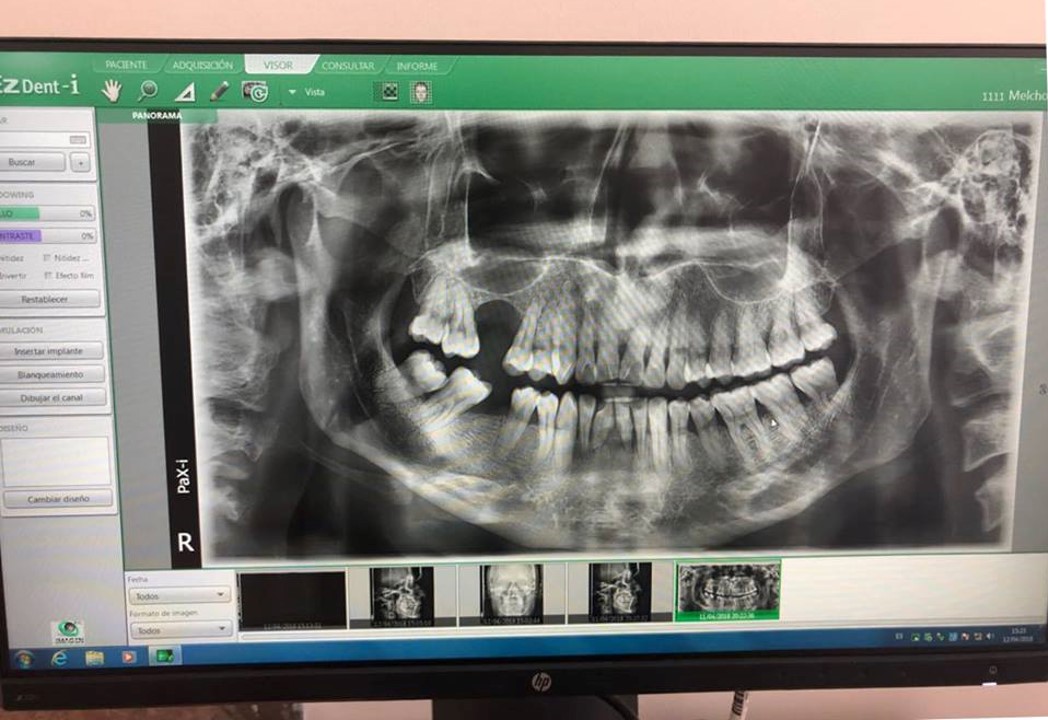

Gracias al Dr. JOSE TAYA MIRANDA, por confiar en nosotros y haber adquirido el paquete completo. Centro de diagnosticos, ubicado en la Av. Manuel Callo 457 - Sicuani-Cusco, instalación de equipo PaX-iSC (Panorámico-Cefalometrico),EzSensor Classic y EzRay Air de la marca VATECH.